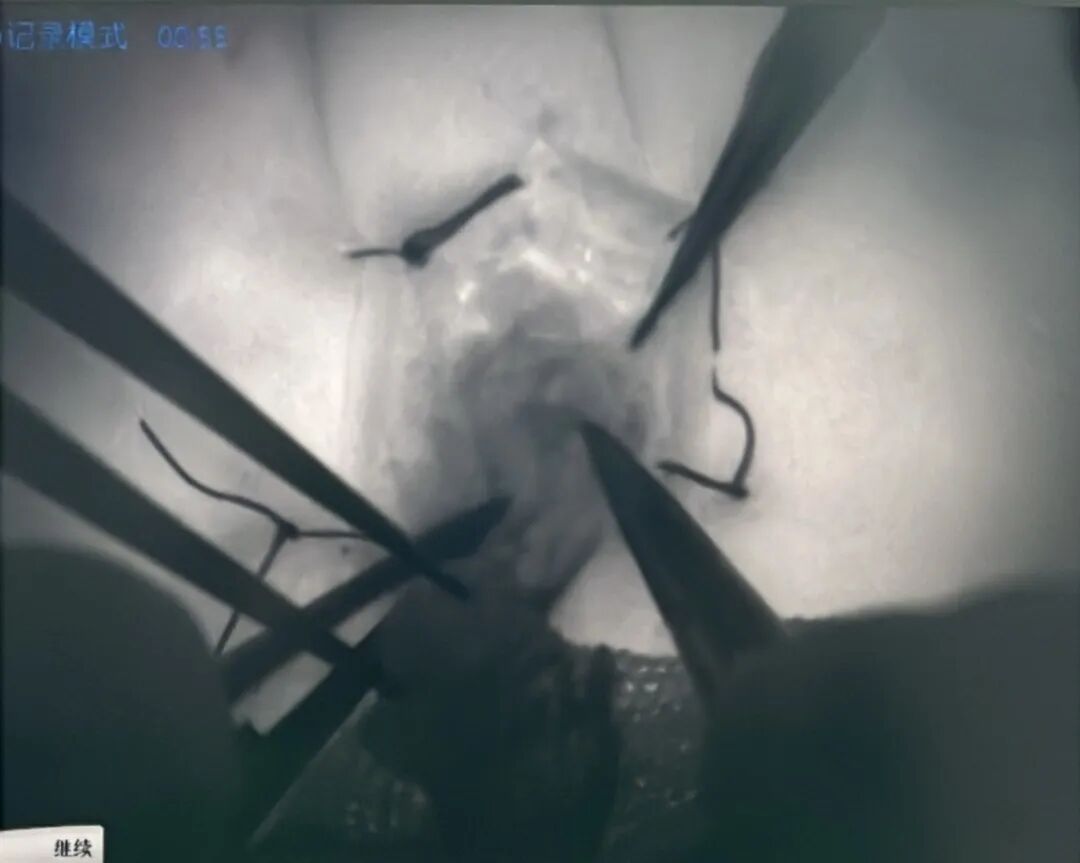

SUMMARY 內(nèi)容概述: 2025年7月5日,葫蘆島市第二人民醫(yī)院顯微功能重建外科成功開展遼西首例超級(jí)顯微外科淋巴管-靜脈吻合術(shù)(LVA)治療肢體淋巴水腫手術(shù),為一位飽受肢體淋巴水腫困擾十年的71歲患者解除了病痛。術(shù)后48天回訪顯示,患者雙腿腫脹完全消失,標(biāo)志著我院在中晚期淋巴水腫微創(chuàng)治療領(lǐng)域取得重大突破。 01 術(shù)后隨訪,見證驚艷效果 為進(jìn)一步驗(yàn)證手術(shù)效果及患者康復(fù)情況,手術(shù)48天后,賈長(zhǎng)軍主任團(tuán)隊(duì)前往劉奶奶家中回訪,眼前的景象讓所有人都倍感欣慰。查體結(jié)果顯示,劉奶奶曾經(jīng)嚴(yán)重腫脹如“大象腿”般粗壯的雙腿,如今已完全消腫,肢體周徑基本恢復(fù)正常。 劉奶奶及家屬表示,感覺腿部輕松了很多,走路輕快且沒有疼痛感,皮膚也不再緊繃。這些顯著變化,不僅給劉奶奶個(gè)人生活帶來了重大轉(zhuǎn)機(jī),更是對(duì)超級(jí)顯微外科淋巴管-靜脈吻合術(shù)(LVA)治療效果的有力證明。 02 病例回顧 2025年7月5日,葫蘆島市第二人民醫(yī)院顯微功能重建外科賈長(zhǎng)軍、張微微主任團(tuán)隊(duì)在西安醫(yī)學(xué)院鳳城醫(yī)院鄭曉菊教授的全程指導(dǎo)及多學(xué)科協(xié)作下,成功開展遼西首例超級(jí)顯微外科淋巴管-靜脈吻合術(shù)(LVA)治療肢體淋巴水腫手術(shù)。 術(shù)中通過高頻超聲輔助定位和ICG(吲哚菁綠)熒光造影,于肢體表面精準(zhǔn)定位淋巴管病灶位置。術(shù)中需吻合的淋巴管多達(dá)30余根,這些淋巴管直徑極為細(xì)小,均在0.1mm~0.5mm之間,最細(xì)的僅有0.1mm,手術(shù)團(tuán)隊(duì)運(yùn)用超高放大倍率的雙熒光顯微鏡,對(duì)淤塞淋巴管和靜脈進(jìn)行吻合,建立淋巴靜脈回流通道,改善淋巴肢體的回流和水腫癥狀。 術(shù)前ICG熒光造影定位淋巴管 鄭曉菊教授、賈長(zhǎng)軍主任帶領(lǐng)團(tuán)隊(duì) 顯微鏡下開展LVA手術(shù) 這一手術(shù)填補(bǔ)了遼西地區(qū)中晚期淋巴水腫微創(chuàng)治療的空白,標(biāo)志著區(qū)域內(nèi)超級(jí)顯微外科技術(shù)實(shí)現(xiàn)重大突破,為肢體淋巴水腫患者提供了更優(yōu)治療選擇。 03 著名專家簡(jiǎn)介 鄭曉菊 主任醫(yī)師 教授 西安鳳城醫(yī)院手足顯微外科病院院長(zhǎng) 學(xué)術(shù)任職: 國(guó)際矯形與創(chuàng)傷外科學(xué)會(huì)SICOT中國(guó)部顯微外科學(xué)會(huì)常務(wù)委員、中國(guó)醫(yī)師協(xié)會(huì)顯微外科醫(yī)師分會(huì)委員、中國(guó)職工技術(shù)學(xué)會(huì)顯微修復(fù)技能專業(yè)委員會(huì)常務(wù)委員、中國(guó)康復(fù)醫(yī)學(xué)會(huì)修復(fù)重建外科專委會(huì)淋巴學(xué)組副組長(zhǎng)、中華醫(yī)學(xué)會(huì)顯微外科學(xué)分會(huì)顯微修復(fù)學(xué)組委員、中國(guó)醫(yī)師協(xié)會(huì)顯微外科醫(yī)師分會(huì)顯微足踝外科專業(yè)委員會(huì)委員、《中華顯微外科雜志》編委、美國(guó)手外科學(xué)會(huì)會(huì)員、陜西省保健學(xué)會(huì)手外科與顯微外科專業(yè)委員會(huì)副主任委員、陜西省保健學(xué)會(huì)創(chuàng)面治療與組織修復(fù)專業(yè)委員會(huì)副主任委員、陜西省醫(yī)師協(xié)會(huì)手外科醫(yī)師分會(huì)常務(wù)委員、西安市醫(yī)學(xué)會(huì)顯微外科學(xué)分會(huì)副主任委員。 專業(yè)特色: 從事顯微外科工作40余年,發(fā)表SCI及國(guó)內(nèi)文章30余篇,出版專著2部,主持省級(jí)科研項(xiàng)目4項(xiàng),市區(qū)級(jí)科研項(xiàng)目15項(xiàng),獲得省、市科技進(jìn)步獎(jiǎng)6項(xiàng)。先后21次出訪歐美及發(fā)達(dá)國(guó)家進(jìn)行學(xué)術(shù)交流。 賈長(zhǎng)軍 主任醫(yī)師 葫蘆島市第二人民醫(yī)院骨科主任 學(xué)術(shù)任職: 中華醫(yī)學(xué)會(huì)手外科學(xué)分會(huì)東北地區(qū)手外科第九屆委員、中國(guó)醫(yī)師協(xié)會(huì)顯微外科醫(yī)師分會(huì)斷肢(指)再造專業(yè)第一、二屆委員、中國(guó)康復(fù)醫(yī)學(xué)會(huì)修復(fù)與重建外科專業(yè)委員會(huì)第二屆小關(guān)節(jié)學(xué)組委員、中國(guó)老年學(xué)和老年醫(yī)學(xué)學(xué)會(huì)老年骨科分會(huì)第四屆委員、全國(guó)衛(wèi)生產(chǎn)業(yè)企業(yè)管理協(xié)會(huì)骨科分會(huì)委員、遼寧省醫(yī)學(xué)會(huì)手外科學(xué)分會(huì)第七屆委員、遼寧省醫(yī)學(xué)會(huì)運(yùn)動(dòng)醫(yī)療學(xué)分會(huì)第三屆委員會(huì)青年委員、遼寧省醫(yī)師協(xié)會(huì)骨科醫(yī)師分會(huì)第一屆委員會(huì)委員、遼寧省醫(yī)師協(xié)會(huì)創(chuàng)傷醫(yī)師分會(huì)第一屆委員、葫蘆島市醫(yī)學(xué)會(huì)顯微外科學(xué)分會(huì)第一屆委員會(huì)主任委員、葫蘆島市醫(yī)學(xué)會(huì)慢性創(chuàng)面外科修復(fù)學(xué)會(huì)第一屆主任委員、葫蘆島市醫(yī)學(xué)會(huì)骨科學(xué)分會(huì)第一屆副主任委員 專業(yè)特色: 率先在我市開展機(jī)器人輔助關(guān)節(jié)置換手術(shù)、超級(jí)顯微外科淋巴管-靜脈吻合術(shù)(LVA)治療肢體淋巴水腫。對(duì)創(chuàng)傷骨折mippo(微創(chuàng))治療、關(guān)節(jié)翻修、關(guān)節(jié)鏡手術(shù)、脊柱骨折、椎間孔鏡間盤摘除、椎管減壓術(shù)、骨腫瘤手術(shù)、各類型手指再造、斷(肢)指再植、游離穿支皮瓣、先后天畸形矯形、晚期功能重建、慢性難愈性創(chuàng)面修復(fù)、糖尿病足等有著豐富的臨床經(jīng)驗(yàn)。 張微微 副主任醫(yī)師 葫蘆島市第二人民醫(yī)院骨科副主任 學(xué)術(shù)任職: 中國(guó)醫(yī)師協(xié)會(huì)顯微外科醫(yī)護(hù)交匯學(xué)組委員、葫蘆島市醫(yī)學(xué)會(huì)顯微外科分會(huì)副主任委員、葫蘆島市醫(yī)學(xué)會(huì)慢性創(chuàng)面修復(fù)外科分會(huì)副主任委員、中國(guó)老年學(xué)和老年醫(yī)學(xué)學(xué)會(huì)老年骨科分會(huì)委員;全國(guó)衛(wèi)生產(chǎn)業(yè)企業(yè)管理協(xié)會(huì)骨科分會(huì)委員、遼寧省細(xì)胞生物學(xué)會(huì)數(shù)字創(chuàng)面修復(fù)專委員會(huì)常務(wù)委員、遼寧省細(xì)胞生物學(xué)會(huì)數(shù)字顯微外科與細(xì)胞學(xué)研究專業(yè)委員會(huì)理事、遼寧省細(xì)胞生物學(xué)會(huì)脊柱脊髓修復(fù)功能重建與細(xì)胞學(xué)研究專業(yè)委員會(huì)理事、遼寧省細(xì)胞生物學(xué)會(huì)老年骨科與細(xì)胞學(xué)研究專業(yè)委員會(huì)理事、遼寧省XB-修復(fù)重建細(xì)胞學(xué)研究與數(shù)字專委會(huì)委員、遼寧省中醫(yī)藥學(xué)會(huì)血液病專員委員會(huì)委員。 專業(yè)特色: 擅長(zhǎng)顯微外科、慢性難愈性創(chuàng)面的階段性治療、糖尿病足感染、痛風(fēng)潰瘍,感染引起的潰瘍、惡性潰瘍、原發(fā)性皮膚腫瘤、轉(zhuǎn)移性皮膚腫瘤、放射性潰瘍;各種創(chuàng)傷引起的創(chuàng)面軟組織缺損、感染、脈管炎;急診創(chuàng)傷骨科、斷指(肢)再植、手指缺損移植再造、手外傷修復(fù)及功能重建、先天性多指矯形、皮膚軟組織缺損骨外露的皮瓣移植修復(fù)、四肢周圍神經(jīng)損傷修復(fù)、瘢痕攣縮及功能重建,關(guān)節(jié)內(nèi)骨折等。